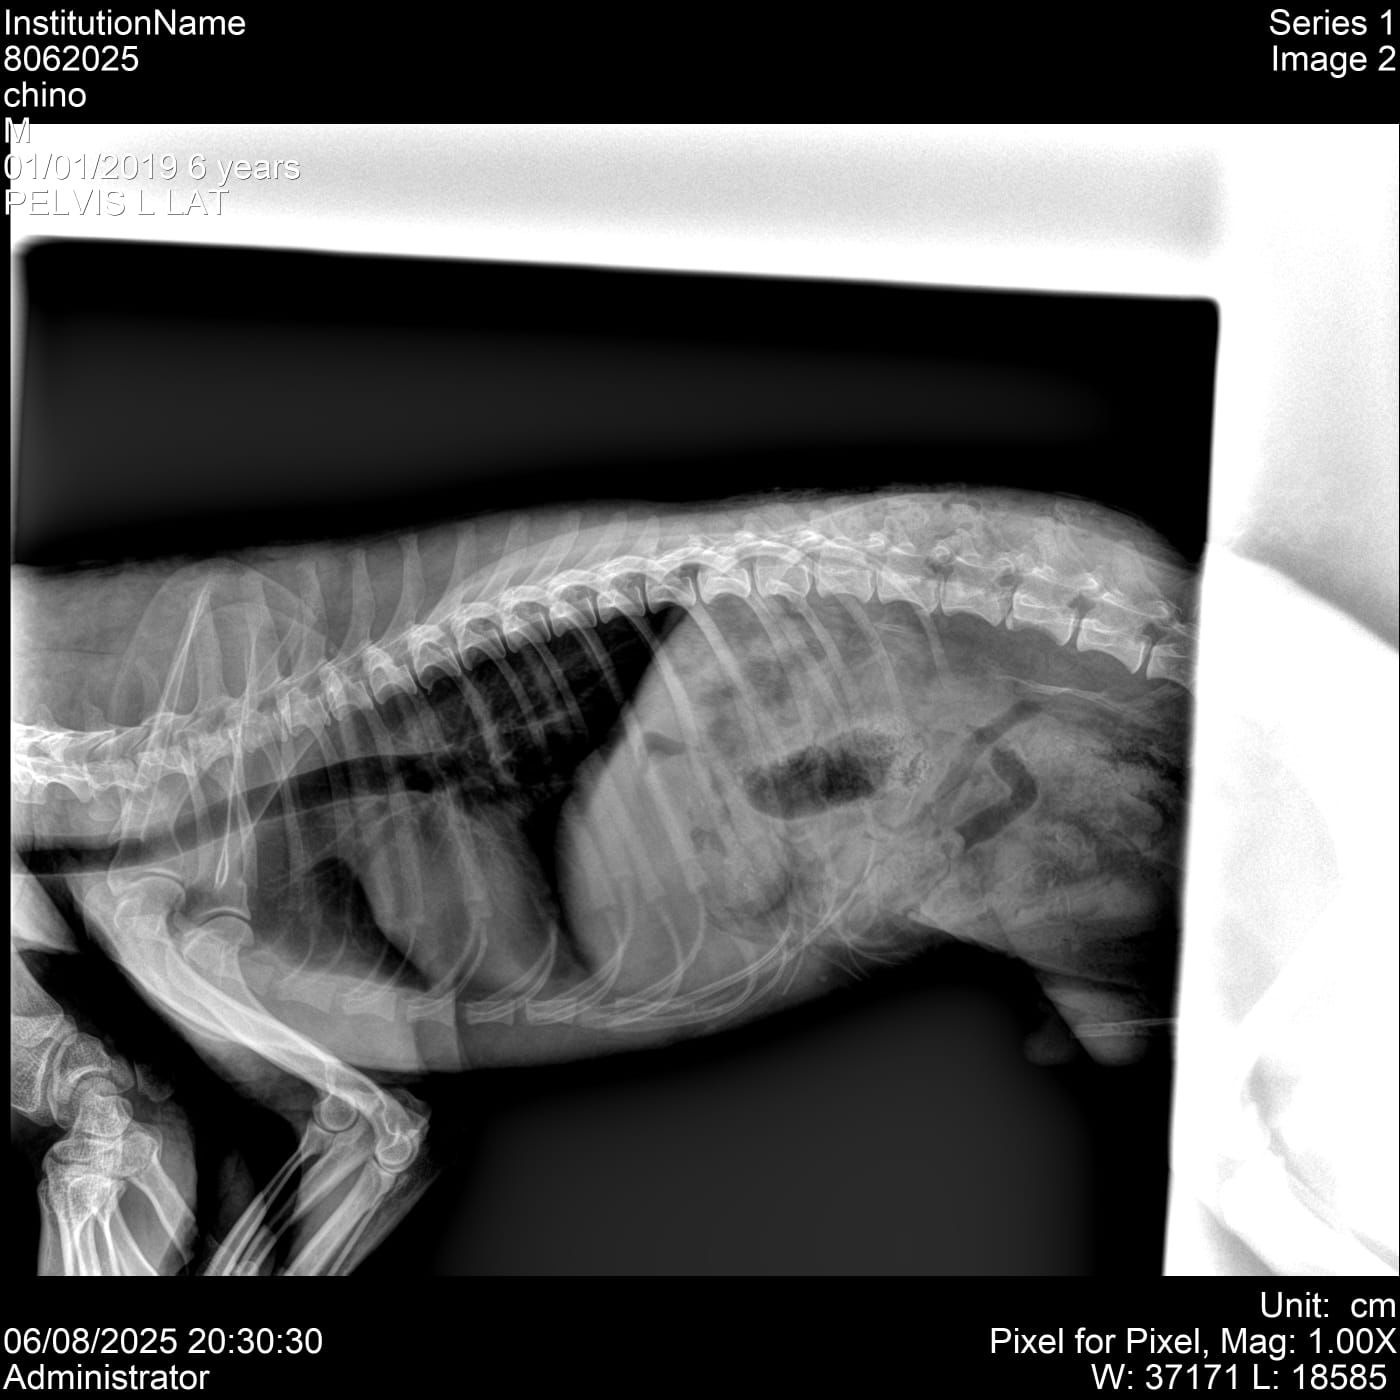

Me llamo Sergio y el motivo por el cual recaudo fondos es por que un miembro de mi familia Chino un perrito raza poodle fue atacado por un perro pitbull causandole lesiones graves en la columna qué ponen en gran riesgo su movilidad a futuro, por ahora es necesario una cirugía de columna con gran costo, la cual está parcialmente cubierta sin embargo aunado a el remanente de esta cirugía aun necesitamos cubrir gastos hospitalarios, medicamentos e insumos médicos para su tratamiento. Le agradecería enormemente a quien desee de corazón donar para ayudar a mi gran amigo.